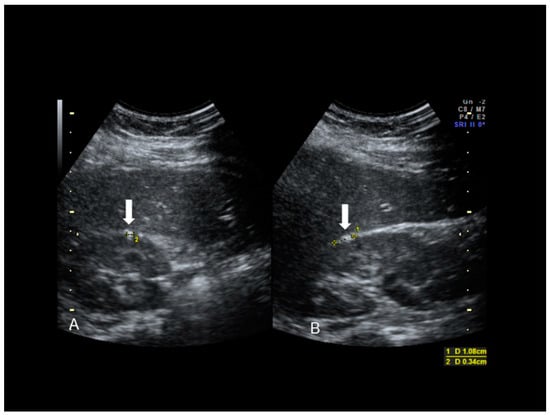

Figure 17. Hepatic superficial endometriosis (see white arrow) confirmed at surgery (A,B).